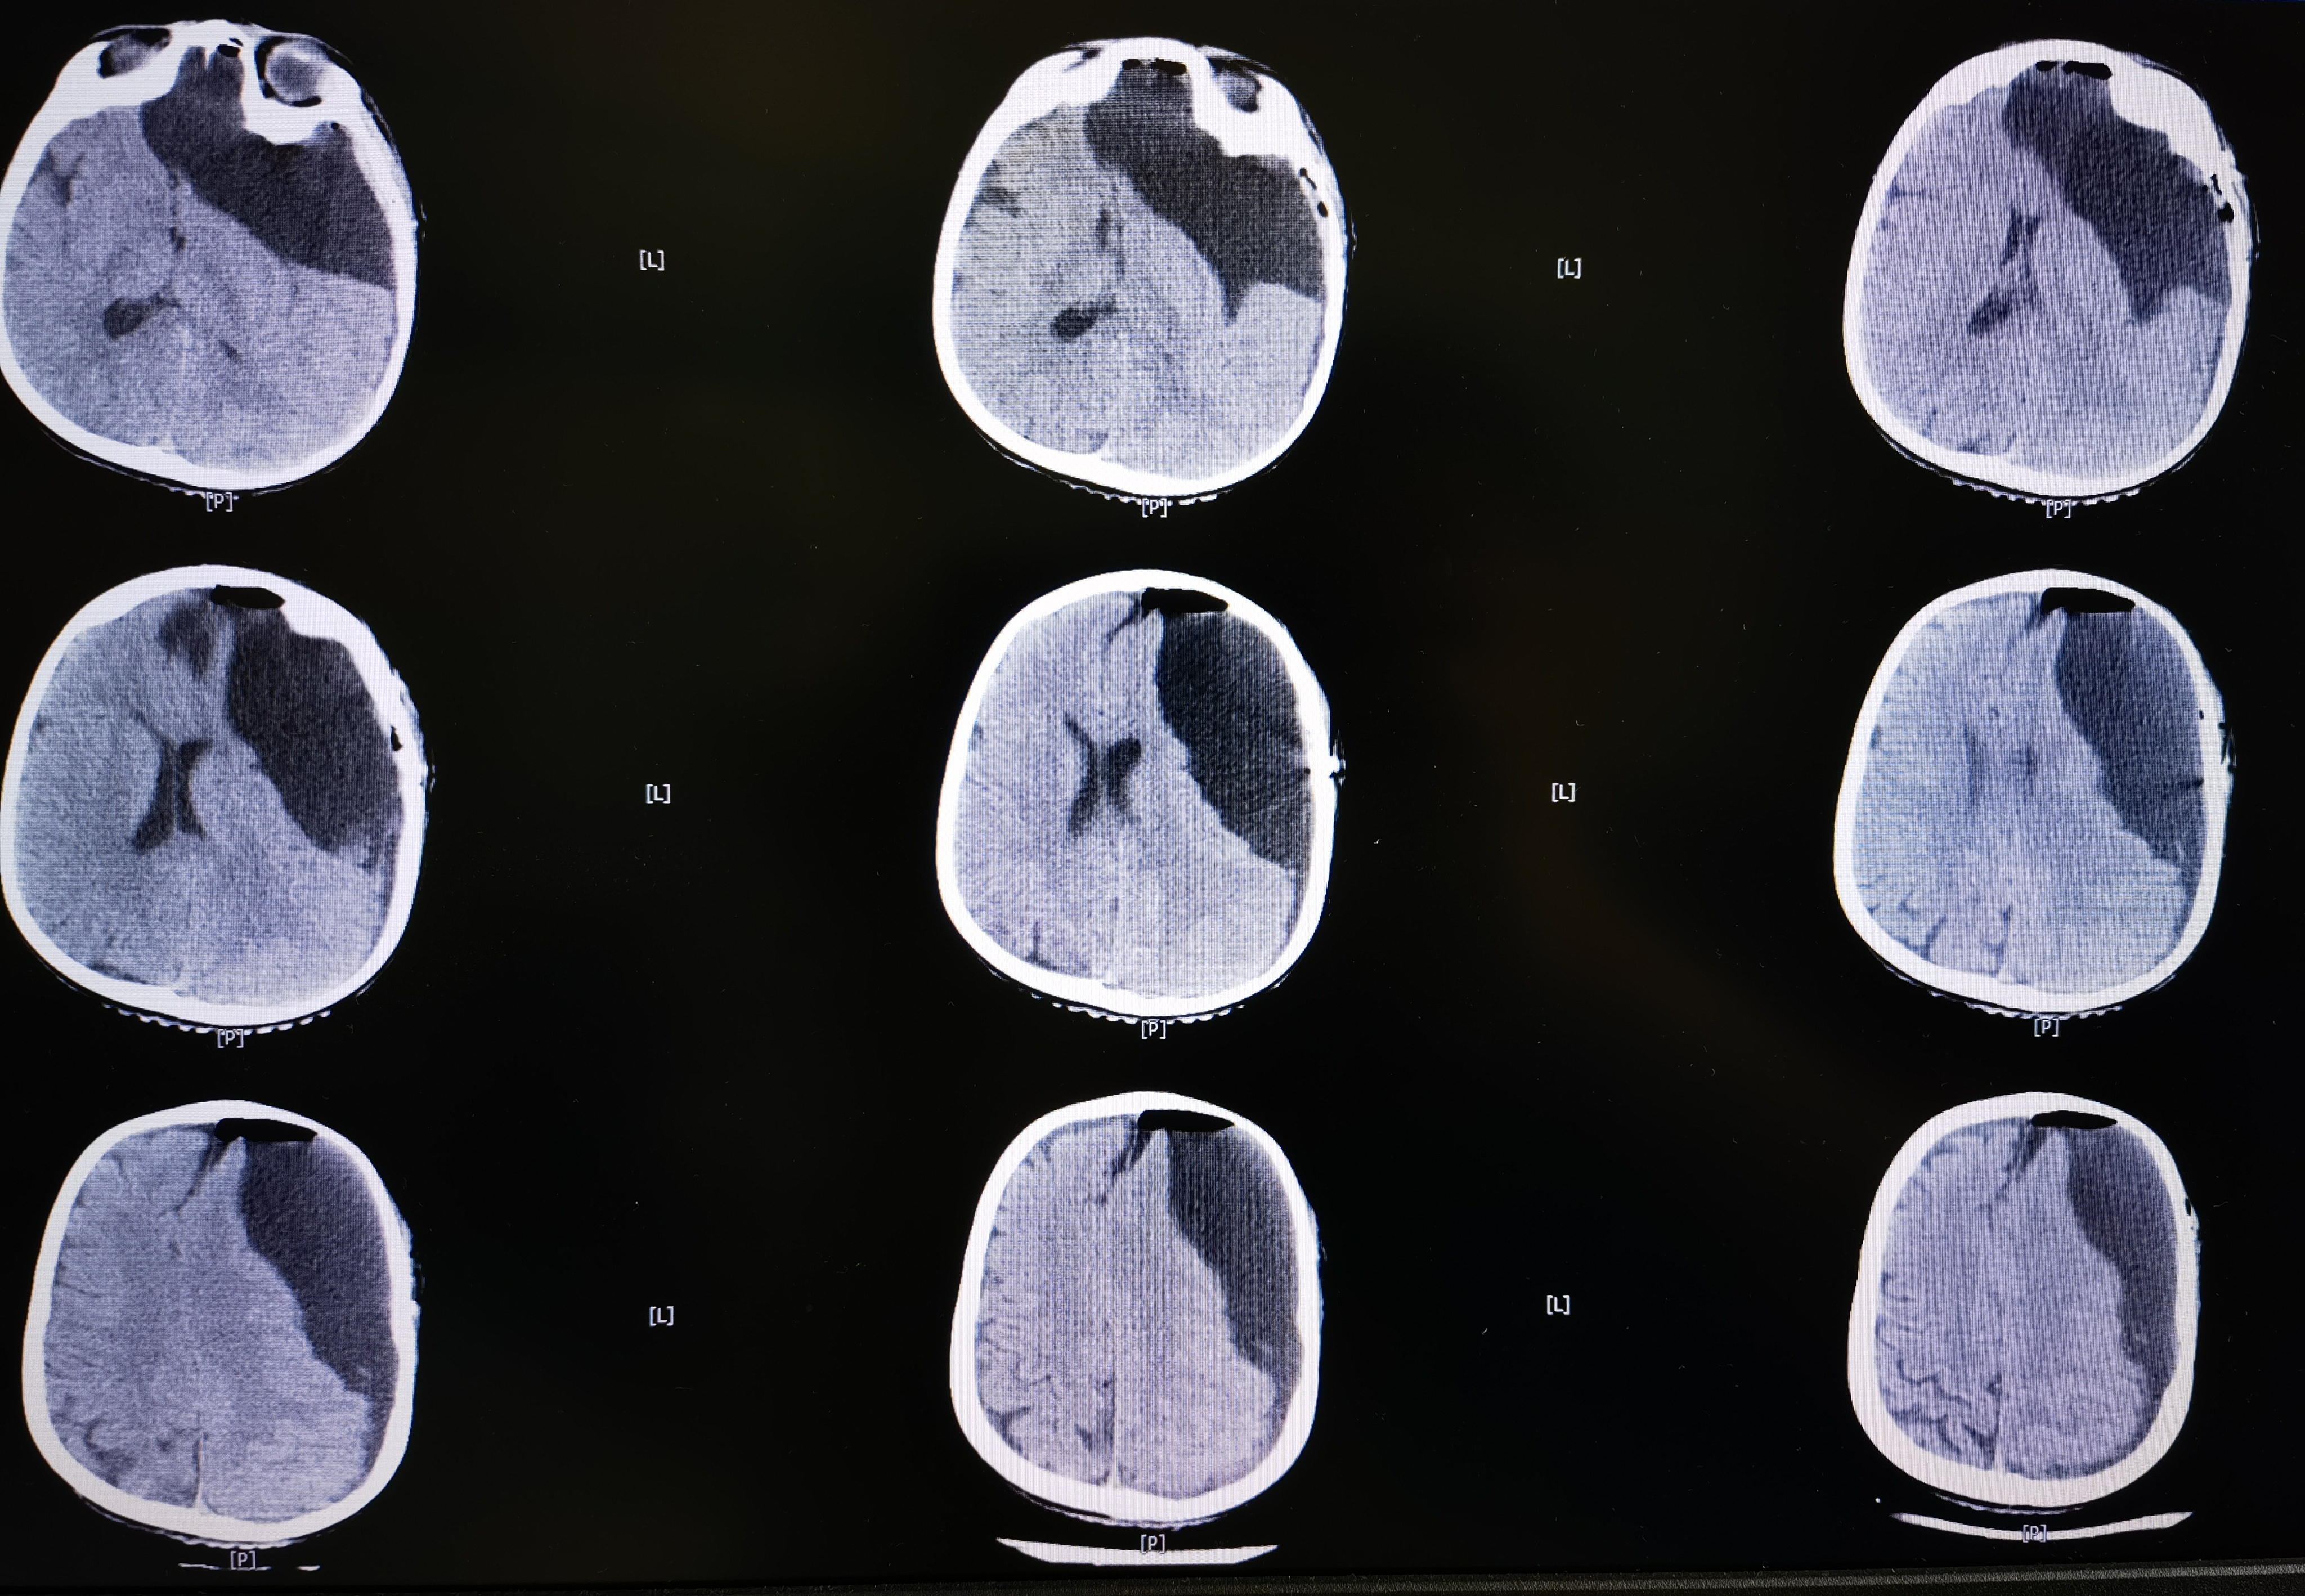

8岁男孩,以“头部外伤后头晕8天”入院,患儿8天前于3米高处坠落摔伤头部,伤后有昏迷史,当地医院CT提示左额颞巨大蛛网膜囊肿,破裂可能。患儿伤后感头晕,当地医院建议转至我院。我院完善头颅MR提示左额颞巨大蛛网膜囊肿,局部越过中线突入右侧镰旁挤压右额叶,左侧额颞岛叶明显受压,囊肿破裂可能。

术后CT